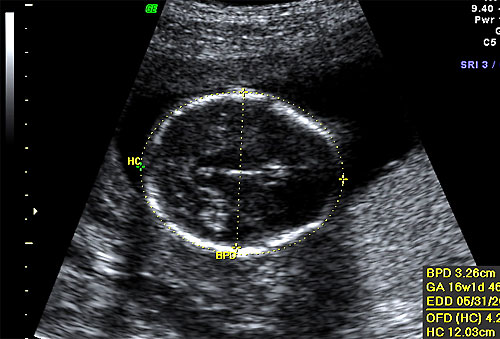

Normal BPD and HC at 16 weeks |

Normal 16 week OFD measurement |

Biometry of 16 week fetal ultrasound |